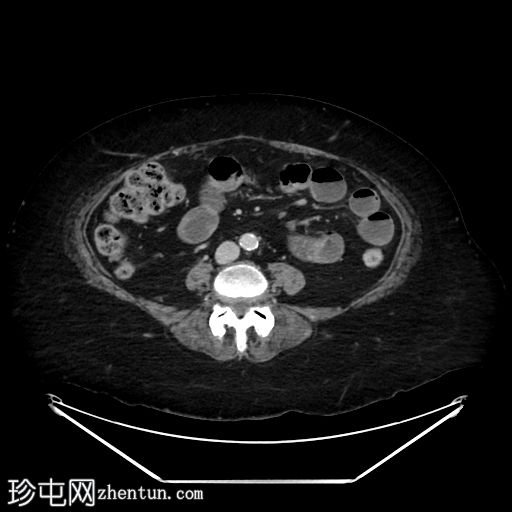

轴位增强扫描(门静脉期)

可见小食管裂孔疝。胆道积气。胆囊增厚,相对减压,并伴有胆囊十二指肠瘘。空肠至回肠近端中度扩张,回肠近端可见节段性增厚,并延伸至右下腹的移行点。移行点处可见一枚卵圆形层状胆结石,周围有少量吞咽物。双侧全髋关节置换术导致盆腔出现条状伪影。未见其他急性异常。

这是一个典型的胆石性肠梗阻病例,伴有胆囊十二指肠瘘,移行点位于右下腹近端回肠(里格勒三联征)。请注意,肠壁在移行点附近轻度增厚,阻塞性胆结石可能与吞咽物混杂在一起,容易被忽略。此外,还应注意胆囊肠瘘可能被误认为是正常的上消化道解剖结构或十二指肠憩室。这些观察结果有助于强调全面检查的重要性。